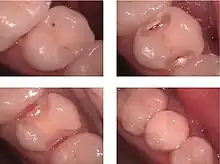

Greene Vardiman Black classification:

G.V. Black classified the cavities depending on their site: [7]

- Class I Caries affecting pit and fissure, on occlusal, buccal, and lingual surfaces of molars and premolars, and palatal of maxillary incisors.

- Class II Caries affecting proximal surfaces of molars and premolars.

- Class III Caries affecting proximal surfaces of centrals, laterals, and cuspids.

- Class IV Caries affecting proximal including incisal edges of anterior teeth.

- Class V Caries affecting gingival 1/3 of facial or lingual surfaces of anterior or posterior teeth.

- Class VI Caries affecting cusp tips of molars, premolars, and cuspids.

Graham J. Mount's classification:

Mount classified cavities depending on their site and size.[8] The proposed classification was designed to simplify the identification of lesions and to define their complexity as they enlarge.

Site:

- Pit/Fissure: 1

- Contact area: 2

- Cervical: 3

Size:

- Minimal: 1

- Moderate: 2

- Enlarged: 3

- Extensive: 4